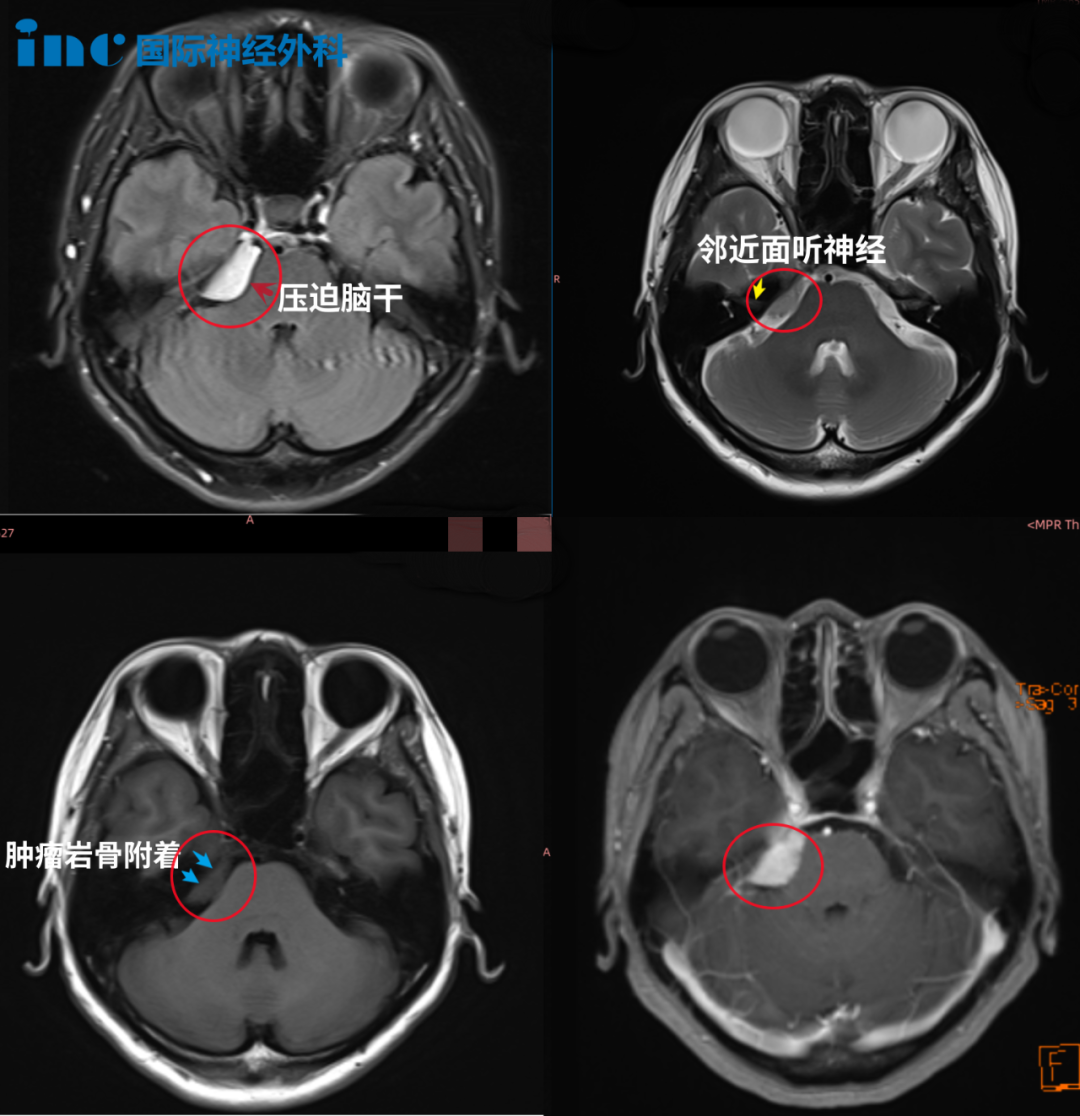

醫(yī)生告知,右側(cè)橋小腦角(CPA)區(qū)占位,腫瘤位置與三叉神經(jīng)、面聽神經(jīng)、滑車神經(jīng)等重要顱神經(jīng)及海綿竇、小腦關(guān)系密切,已經(jīng)壓迫到腦干,手術(shù)治療傷及神經(jīng)的風(fēng)險很大,也就是說如果手術(shù)做不好,可能面癱、聽力喪失、肢體癱瘓,甚至昏迷等。

鐘女士2022年1月影像檢查結(jié)果顯示:右側(cè)橋小腦角區(qū)占位,腫瘤侵犯到右側(cè)Meckel腔